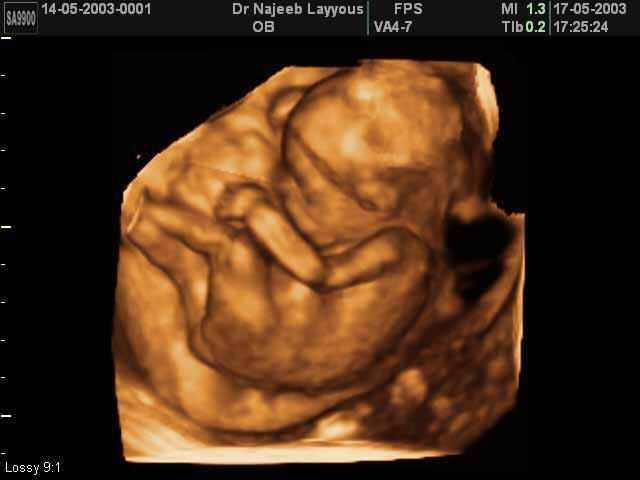

- تصرفات الجنين داخل الرحم

- صور لتصرفات الجنين داخل الرحم

صور لتصرفات الجنين داخل الرحم بجهاز الالتراساوند ثلاثي الأبعاد | الدكتور نجيب ليوس